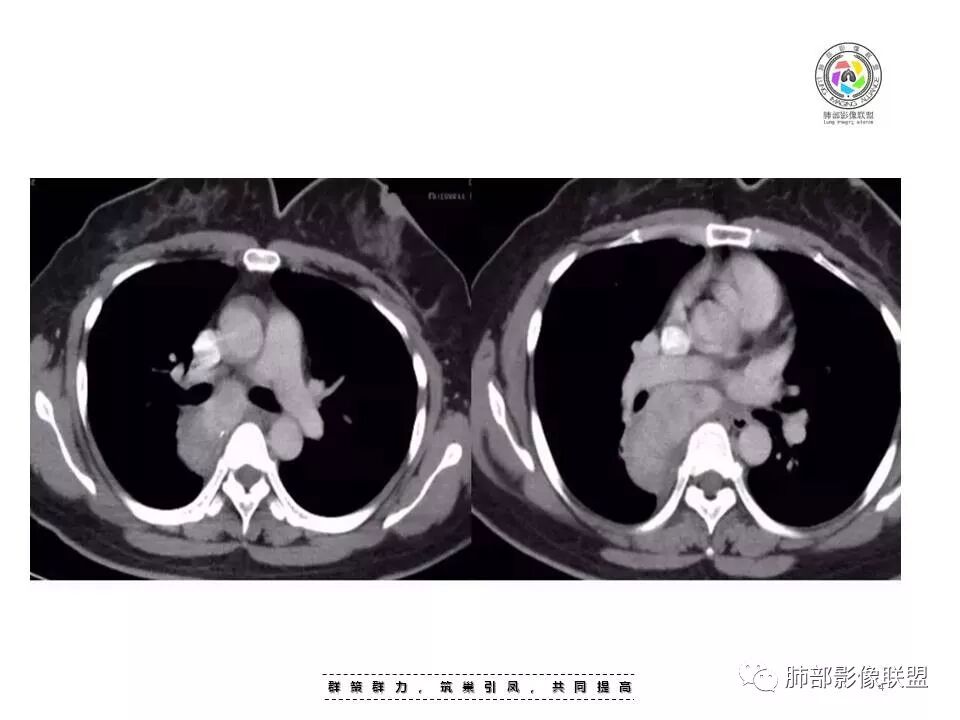

女,35岁 因“体检发现纵隔占位”入院,患者3天前体检发现肺部异常,外院胸部CT示右后纵隔占位,纵隔淋巴结影,未诉明显不适,无心慌胸闷,无头晕头痛,无恶心呕吐,无腹胀腹痛,无吞咽困难。

后纵隔占位,内见小钙化灶,增强明显强化,考虑CD。

神经源性肿瘤,内可见点状钙化,增强后强化明显,考虑神经源性肿瘤。

后纵膈,胸膜掀起,密度相对均匀,钙化,增强强化明显,接近血池密度,没有明显ab区,且椎间孔等还行,暂不考虑鞘瘤,节细胞强化有点过,神经源性放后面。后纵膈肿瘤与食管脂肪间隙存在排除食管来源。血管来源强化略偏弱一些,异位囊肿影像不符合。淋巴来源CD影像及强化符合

考虑CD可能大,神经源性待排。

后纵隔占位,不均匀强化伴分隔,病灶与7区肿大淋巴结融合,病灶与胸膜之间可见少量积液,考虑CD,鉴别神经鞘瘤。

后纵隔肿物,呈肾形,可见淋巴结门,平扫内可见钙化,显著强化,考虑CD,上下径长签别鞘瘤。

后纵膈,脊柱旁

明显血管样强化

按理:CD、付节瘤

CD:附近、内部血管多;但是这一点付节瘤也是

CD:附近晕征、附近多发子灶,这一点付节瘤不具备

最具特点的是:淋巴结门状结构

结果:巨大淋巴结增生病(Castleman,s, disease,CD)

(3)影像表现上,多发单发的圆形或类圆形软组织密度影;透明血管型在CT增强扫描时早期可显著均匀强化,与大血管强化程度相似,原因在于有较多的供养血管,及病灶的毛细血管异常增生和扩展所致;而浆细胞型强化没有前者明显